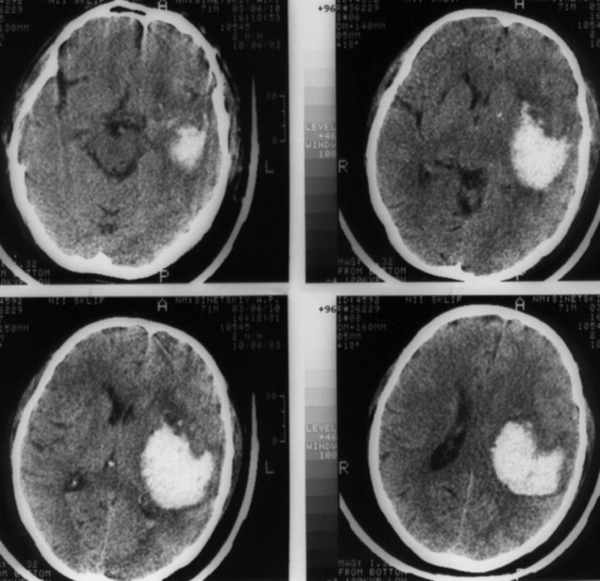

- КТ или МРТ головного мозга;